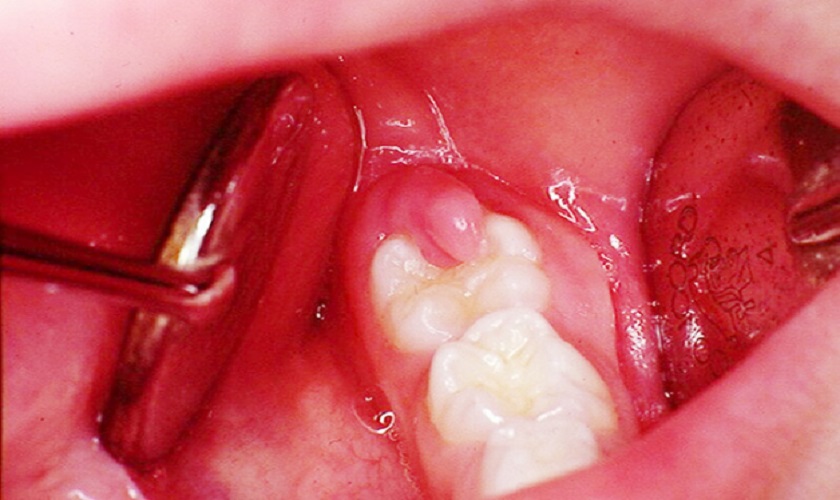

- Mọc răng khôn: Nhiều trường hợp mọc răng khôn gây ra tình trạng viêm quanh răng do răng khôn mọc khó, mọc kẹt, mọc ngầm. Các dấu hiệu bao gồm đau nhức ở vị trí hàm phía trong cùng, nướu sưng to, có thể bị sưng mặt, khó há miệng, nổi hạch và hành sốt.

Răng khôn mọc kẹt gây viêm nhiễm quanh răng dẫn đến đau răng nổi hạch